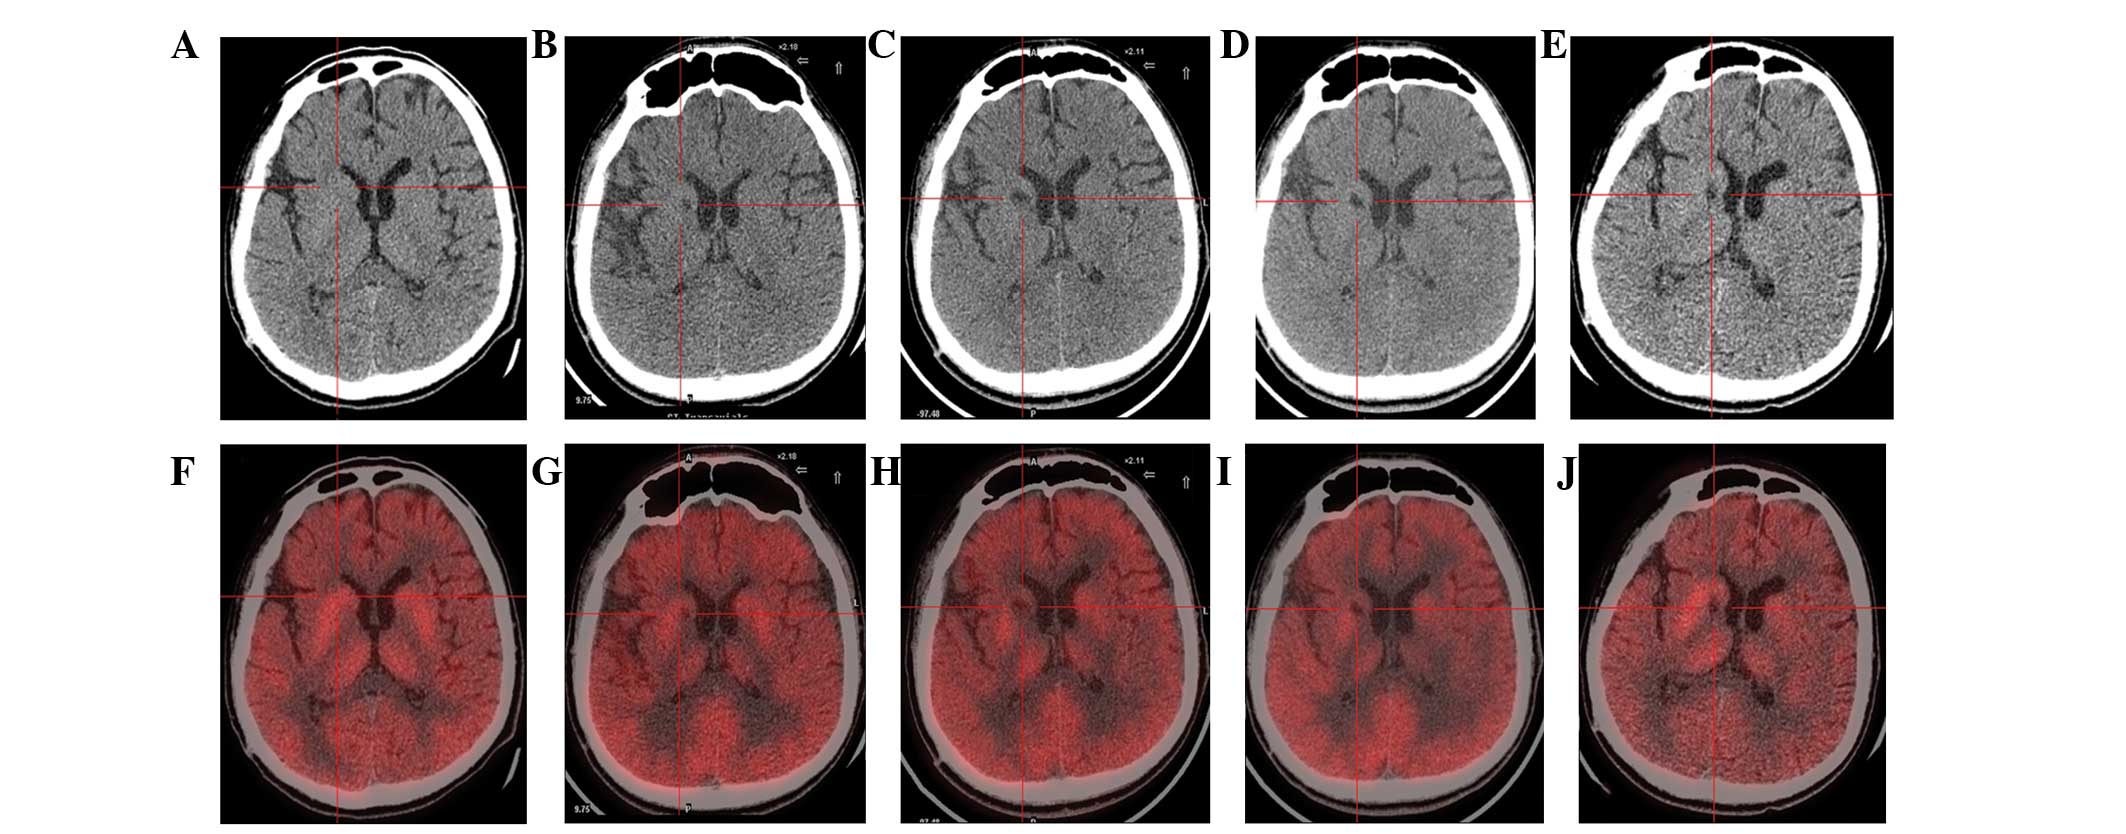

圖1:計算機斷層掃描 (CT) 和正電子發(fā)射斷層掃描 (PET) 掃描。

(A) 術(shù)前CT顯示腦萎縮。

(BE)術(shù)后1年、2年、3年、4年CT與術(shù)前相比均無(wú)明顯變化。

(F)術(shù)前18F-氟脫氧葡萄糖 (FDG) PET 掃描顯示,整個(gè)大腦皮層FDG攝取彌漫性減少,細胞核FDG攝取相對高于其他區域。術(shù)前1天,豆狀核和丘腦的標準化攝取值 (SUV) 平均值/最大值分別為4.3/5.8和3.3/4.5。

(GJ) 神經(jīng)干細胞移植治療后分別 1、2、3 和 4 年的 18F-FDG PET 掃描顯示,雙側植入部位的豆狀核和丘腦對 18F-FDG的攝取增加(紅十字)與植入前相同部位進(jìn)行比較。 豆狀核和丘腦的SUV*平均值/最大值在 1、2、分別是術(shù)后3年和4年。 該結果表明移植后葡萄糖代謝比移植前稍高。

CT(圖1b-e)和MRI(圖2b-d)掃描顯示4年隨訪(fǎng)期間沒(méi)有顯著(zhù)變化。 手術(shù)前1天(圖1f)和手術(shù)后1、2、3和4年(圖1g-j) 獲得18F-FDGPET掃描。術(shù)后雙側植入部位豆狀核和丘腦18F-FDG攝取值較術(shù)前增加。這一結果表明,自移植以來(lái),葡萄糖代謝逐年略有增加。